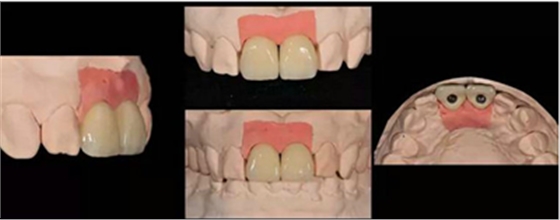

蠟型制作完成后,翻制硅橡膠導(dǎo)板,根據(jù)穿齦輪廓來(lái)修整人工牙齦,保證修整后鄰緣的位置與診斷蠟型一致。即根據(jù)硅橡膠導(dǎo)板及齦緣修整牙齦范圍,隨后進(jìn)行穿齦輪廓的修整。

修復(fù)種植臨時(shí)基臺(tái)

本病例選用光固化樹(shù)脂材料制作過(guò)渡義齒,光固化樹(shù)脂材料豐富,方便操作,戴牙出現(xiàn)問(wèn)題時(shí),也方便及時(shí)進(jìn)行修復(fù)。

種植過(guò)渡義齒完成(螺絲固位)

種植過(guò)渡義齒試戴,調(diào)整唇側(cè)凸度,切端位置

患者剛戴入過(guò)渡義齒時(shí),發(fā)現(xiàn)牙齦泛白,范圍不超過(guò)鄰牙終點(diǎn)。若患者休息10分鐘后,牙齦顏色恢復(fù)正常,則說(shuō)明穿齦輪廓設(shè)計(jì)合理。

通過(guò)使用個(gè)性化轉(zhuǎn)移桿進(jìn)行取模,模型精確復(fù)制牙齦輪廓

11,21 ASC 全瓷基臺(tái)一體冠蠟型

飾面瓷堆塑

牙齒形態(tài)修整

根據(jù)天然牙形態(tài)進(jìn)行牙冠形態(tài)修整、表面紋理再現(xiàn)和咬合關(guān)系調(diào)整

角度螺絲通道全瓷基臺(tái)一體冠制作完成

染色、上釉,再現(xiàn)天然牙的顏色特點(diǎn)。